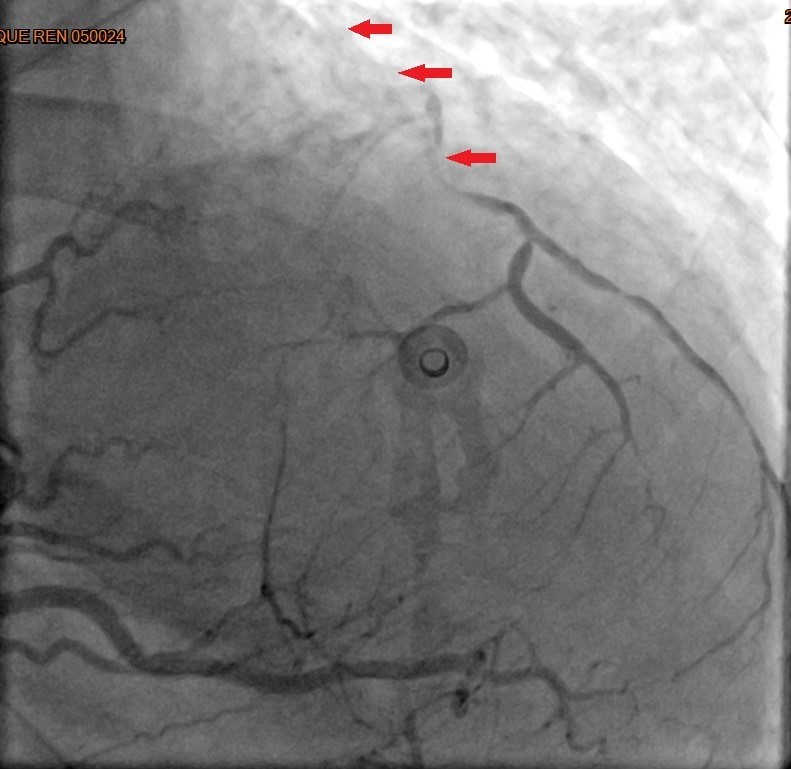

箭頭標示為心導管顯示三條冠狀動脈嚴重阻塞。

38歲的林小姐平常除了工作以外,最大的興趣是追星,雖有高血脂及心臟病家族史但平時身體無恙,去年冬天前往演唱會途中,於捷運站內突然喪失意識,站內人員立即協助施行CPR,隨後EMT前往接手急救與電擊,並立即送往台北慈濟醫院急診,一連串急救處置後,經心導管檢查確認為急性心肌梗塞。由於三條冠狀動脈均出現嚴重阻塞,其中最主要的左前降支近端更呈現完全阻塞狀,已無法透過氣球擴張或支架方式處理,考慮患者年紀尚輕,心臟血管外科宋鎮宇醫師緊急實施冠狀動脈繞道手術,讓她免於因持續灌流不足引發的惡性心律不整、心臟衰竭等併發症。術後經歷拔管、病房積極的心肺復健,於兩週後返家。後續門診持續藥物治療,並與宋醫師一同討論調整生活作息及運動習慣,病況穩定後順利重回追星生活,但也因此更重視健康的飲食與人生。

「通常需要做到緊急手術的,大多是急性心肌梗塞。」宋醫師說明,緊急心臟手術為了減少缺血休克時間,通常得由正中打開胸骨,快速建立體外循環,進而施行繞道手術。以林小姐為例,醫療團隊當下以主動脈氣球幫浦與強心劑協助穩定血壓,再採取內胸動脈及大隱靜脈完成所有血管的接合,阻塞的左前降支則以內胸動脈供血,讓足夠的血流能夠重新灌注缺氧的心肌,重獲新生。國外統計指出,以此方式接合的血管,十年暢通率可維持達90%。此外,若是穩定型的冠狀動脈心臟病,病人可在與醫師討論評估後以達文西機械手臂輔助的方式以小傷口進行,但此項手術仍然有條件的限制,得考量病人的體型、病灶的位置,且需在資格認證的醫院及醫師指導下進行。